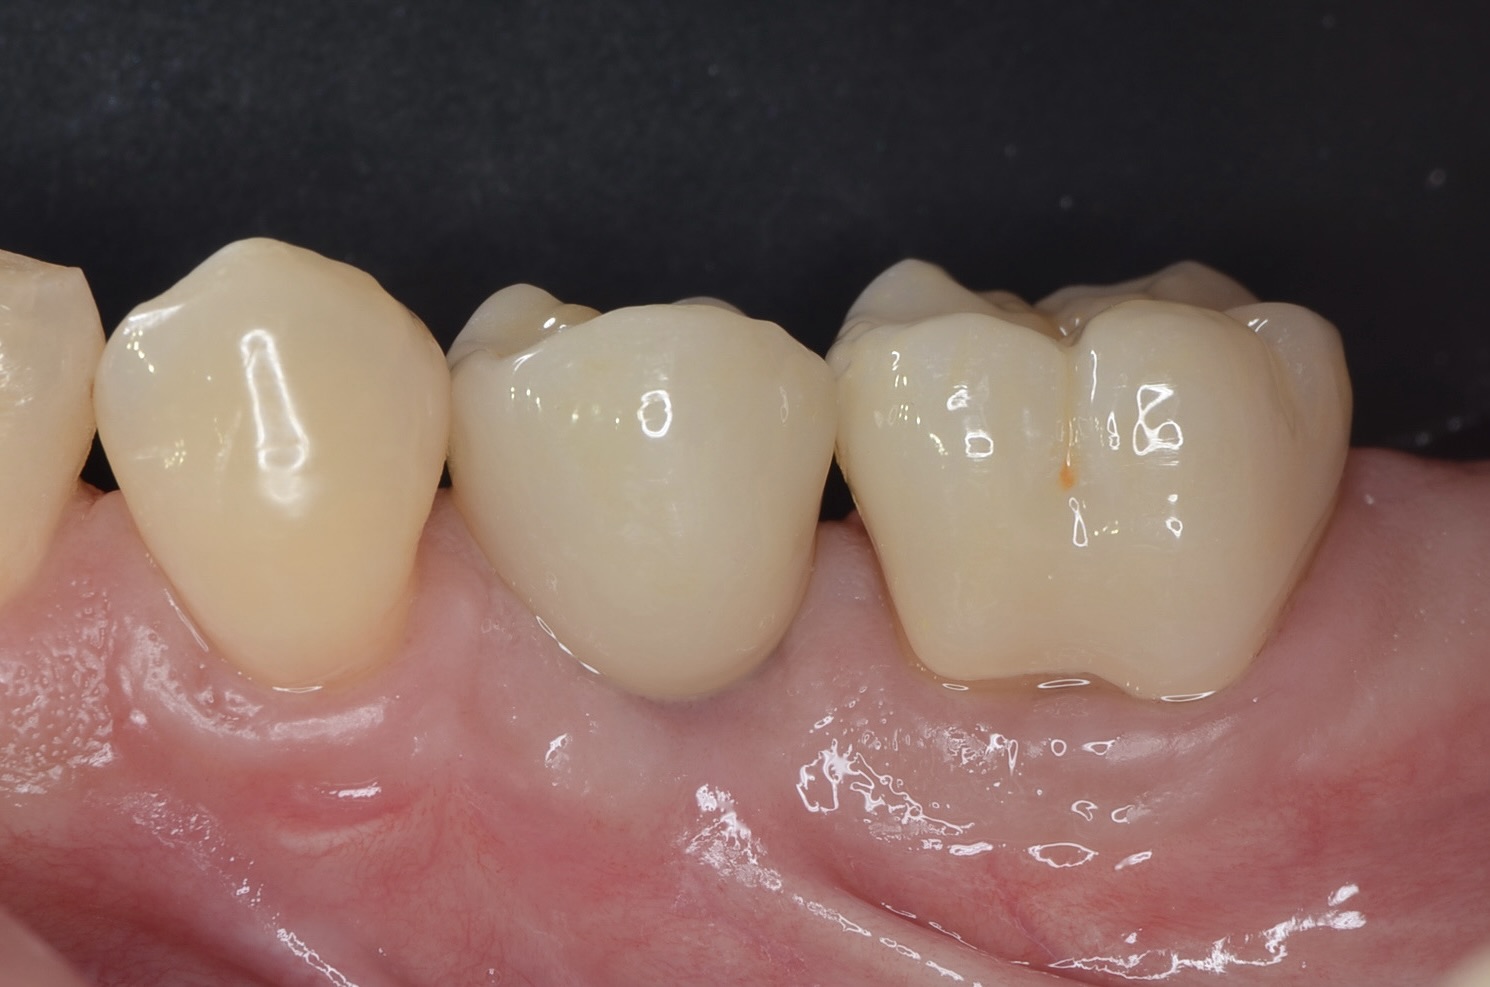

側方面観

自然で綺麗です。 -